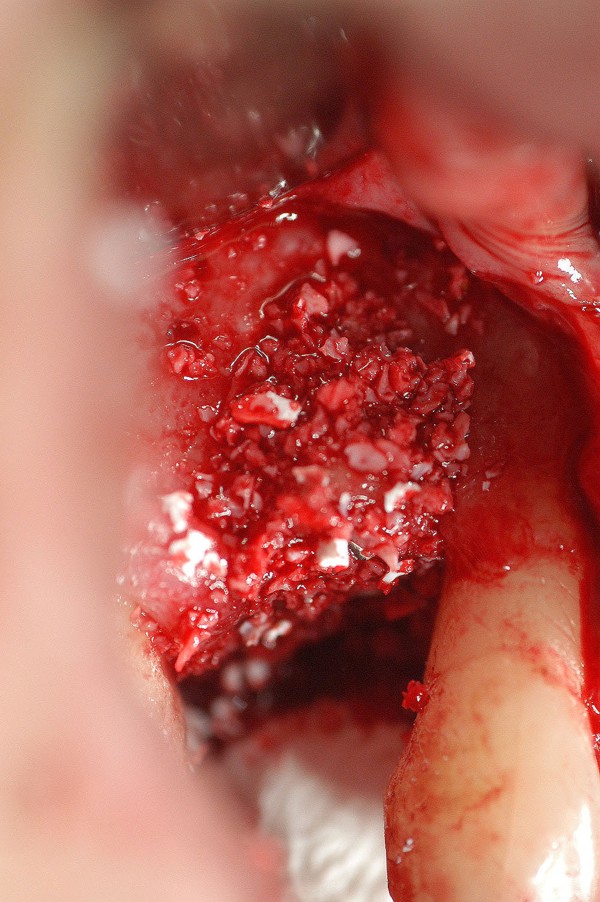

EFECTOS DEL TABAQUISMO CRÓNICO SOBRE LA IRRIGACIÓN ÓSEA TERMINAL. Es por todos conocido el efecto deletéreo que el uso del tabaco provoca sobre la irrigación terminal de mucosas y hueso. Su uso además produce un aumento en la frecuencia cardíaca y la presión arterial, volumen sistólico y gasto cardíaco, a sí como del flujo sanguíneo coronario. vasoconstricción cutánea con una disminución asociada de la temperatura cutánea, y un aumento del flujo sanguíneo muscular. Muchas veces , la intención terapéutica excede los propósitos del paciente de alejarse del tabaco , y se abordan soluciones que terminan en fracasos. Paciente mujer de 53 años de edad, carente de enfermedades, fumadora de dos paquetes diarios de cigarrillos, bruxómana. Se presenta con dolores en la zona de un premolar superior, que porta corona de porcelana sobre un perno colado de oro, con su correspondiente tratamiento de conducto, realizados en mi consulta, veinte años atrás. Se procede a extraer la pieza dentaria, y se observa la pérdida total de la tabla vestibular. Transcurridos seis(6) meses, tiempo mas que suficiente para la conveniente formación de nuevo hueso, se procede a implantar, observándose entonces, que no solo no existía osteogénesis, sino que además se había reabsorbido también la tabla palatina y parte del hueso periférico al canino. En un intento heroico de resolver el caso, se procede a tomar un injerto autólogo de la zona del trígono retro molar, y fijarlo mediante micro tornillo de síntesis en la zona afectada, realizando perforaciones alrededor del lecho quirúrgico a fin de aumentar la irrigación por estímulo traumático del hueso periférico Se vuelve a cubrir con Bioss y membrana Bio Guide, y se sutura convenientemente. Al cabo de otras dos semanas, se expone la porción caudal del injerto, acusando evidentes signos de falta de irrigación. Se retira del lecho receptor, se curetéa y se deja cicatrizar por segunda intención. El caso se encuentra a la espera de solución protética fija. FIG16

Se realiza entonces una Regeneración Ósea Guiada (R.O.G), mediante Bioss y membrana reabsorvible Bio Guide. (INIBSA).

LA FIG 13 CORRSPONDE A LA FIJACIÓN DEL MISMO MEDIANTE UN MICROTORNILLO DE FIJACIÓN, Y LA 14 AL CUBRIMIENTO DEL TODO MEDIANTE HUESO BOVINO MARCA BIOS.